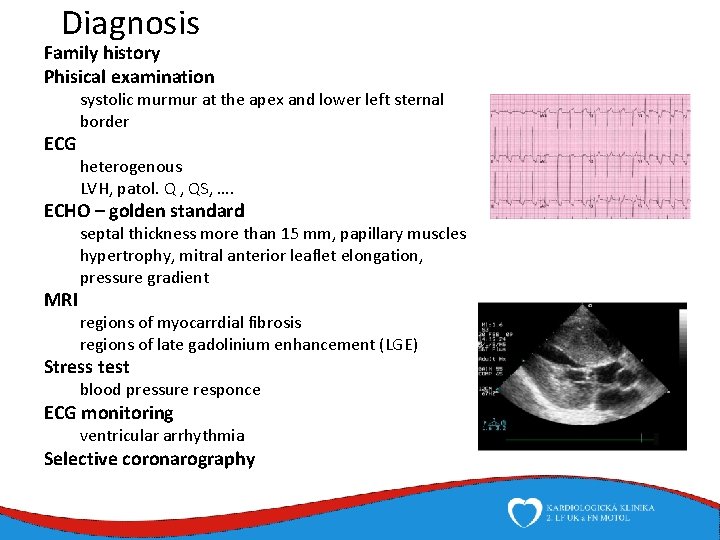

Diagnosis Family history Phisical examination ECG systolic murmur at the apex and lower left sternal border heterogenous LVH, patol. Q , QS, …. ECHO – golden standard MRI septal thickness more than 15 mm, papillary muscles hypertrophy, mitral anterior leaflet elongation, pressure gradient regions of myocarrdial fibrosis regions of late gadolinium enhancement (LGE) Stress test blood pressure responce ECG monitoring ventricular arrhythmia Selective coronarography